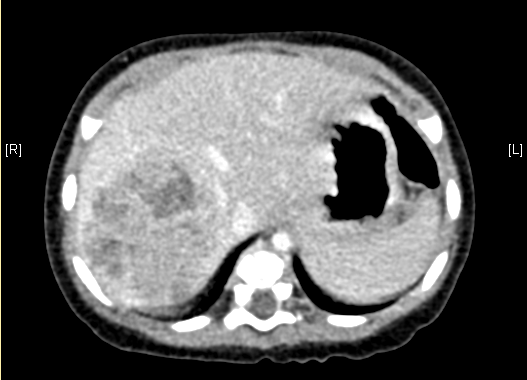

上腹部增强CT:肝右叶巨大占位,肝母细胞瘤可考虑。

术前CT检查:

静脉期